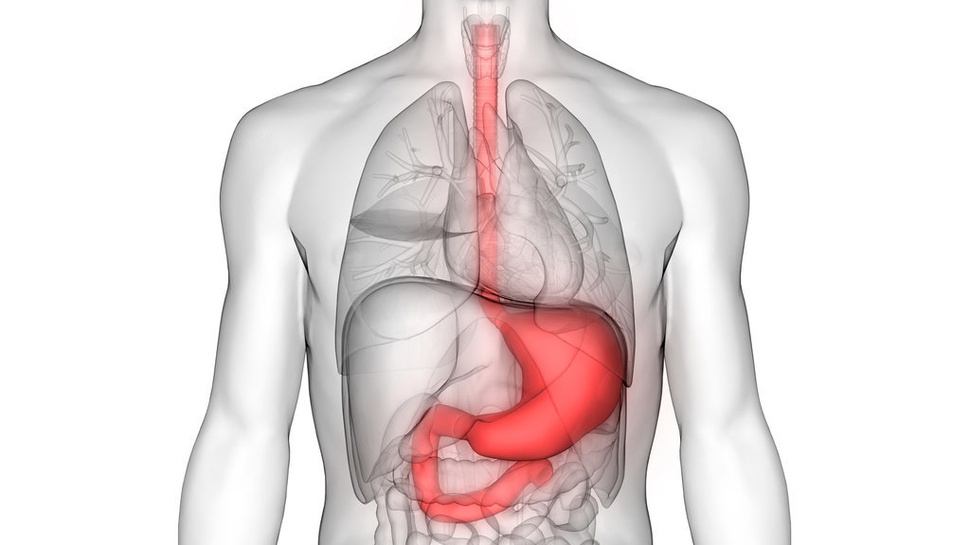

Gastroesophageal Reflux Disease (GERD) atau yang juga dikenal sebagai asam lambung adalah penyakit saluran pencernaan yang umum di Indonesia. Katon Abdul Varid dalam studi yang terbit tahun 2020 menemukan bahwa ada 30.154 kasus GERD di Indonesia.

Penderita asam lambung biasanya akan mengalami sakit atau nyeri perut di sekitar ulu hati, mual, hingga muntah. Gejala asam lambung ini juga sering dialami penderita saat menjalani puasa.

Mengutip Medical News Today, sakit asam lambung saat puasa bisa terjadi karena perut kosong dalam jangka waktu lama. Lantas, apakah penyakit GERD bisa berpuasa? Kabar baiknya, penderita GERD atau asam lambung tetap bisa berpuasa.